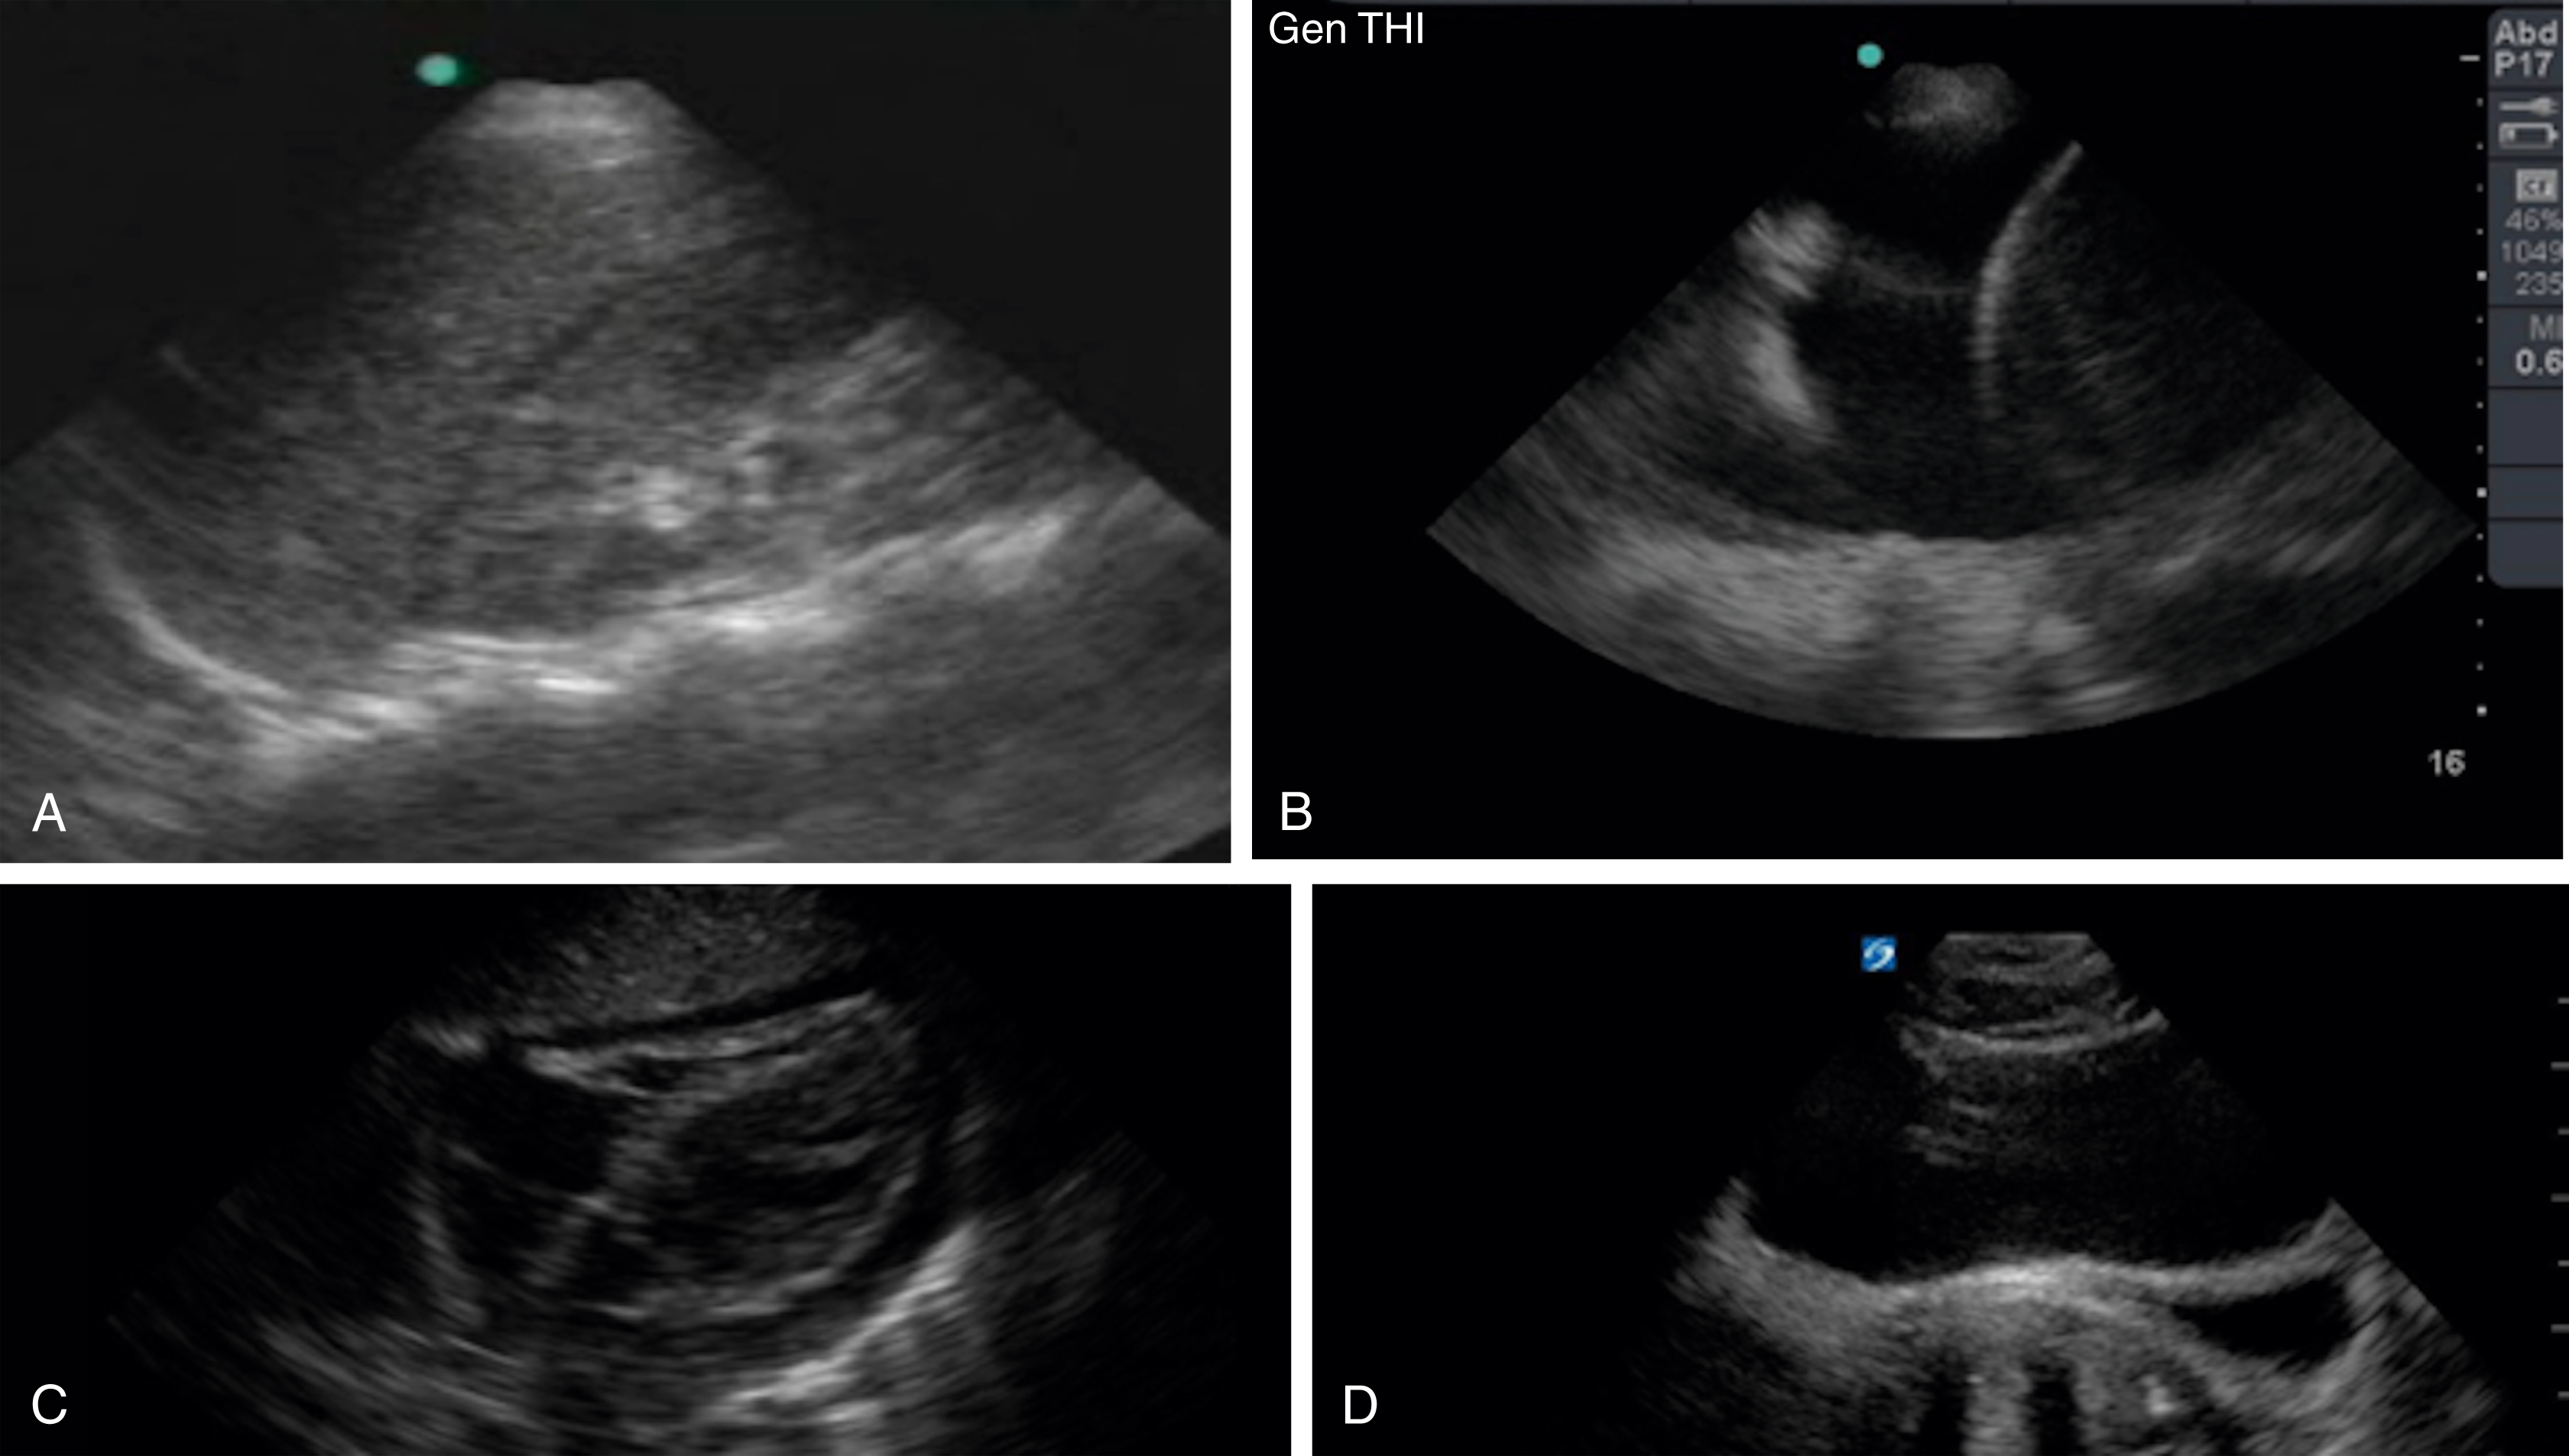

The FAST examination technique uses a low-frequency broadband transducer (2–6 MHz) to evaluate dependent peritoneal spaces, pleural spaces, and the pericardium for free fluid, which in the trauma patient is presumed to be blood. There are four main components of the basic FAST examination: (1) the right upper quadrant (RUQ) view, (2) the left upper quadrant (LUQ) view, (3) the pelvic view and (4) the cardiac view ( Fig. e3.1 ). The E-FAST includes anterior chest views to evaluate for pneumothorax. The RUQ view evaluates for fluid in the thorax (above the diaphragm) ( Video e3.1 ), hepatorenal space (Morison pouch) and the paracolic gutter (inferior edge of the liver and right kidney) ( Video e3.2 ), moving cephalad to caudad. The LUQ view, found slightly more superior and posterior than the RUQ, should mimic the RUQ views, but also include the subdiaphragmatic space, because free intraperitoneal fluid tends to accumulate here initially. The pelvis should be evaluated in the transverse and longitudinal planes, where fluid may be detected deep to the uterus (in females) or in the retrovesical space (in males) ( Video e3.3 ). The cardiac evaluation can be performed in either the subcostal (or subxiphoid) or parasternal window ( Video e3.4 ). Evaluation for pneumothorax uses a low or high-frequency transducer at a shallow depth, placed along the anterior chest wall and will be discussed in more detail in subsequent sections.

Negative FAST images. (A) Subxiphoid view with no pericardial effusion. (B) Negative RUQ view showing the thorax and hepatorenal space without the paracolic gutter visualized. There is mirroring and loss of the spine, indicating a negative thorax. (C) Negative paracolic gutter area by the liver tip in the RUQ view. (D) LUQ view showing negative thorax, as in B, and splenorenal space. (E) Negative transverse bladder view. (F) Negative sagittal bladder view.

Typically, free fluid is anechoic, but it can have echogenicity if active extravasation, a blood clot, or bowel contents are present within the fluid. Compared with other fluid-filled structures in the abdomen and pelvis, peritoneal free fluid generally has sharp pointed edges and an irregular shape, whereas most visceral or vascular structures have intrinsically smooth oval or round contours. The volume of fluid required for a positive US study depends on the site of injury, sonographic window, and experience of the operator, but 250 mL or more is generally visible, and nearly 600 mL of fluid is required for a positive upper quadrant window. With pericardial fluid, once a certain volume is reached, the pressure in the pericardial space increases dramatically, resulting in cardiac tamponade. Generally, at least 50 mL of fluid is required to cause hemodynamic compromise in a patient without prior pericardial inflammation ( Fig. e3.2 ).

Positive FAST images. (A) Positive RUQ view showing a thin stripe of fluid in the hepatorenal space. The thorax is negative and paracolic gutter not visualized. (B) Positive LUQ view showing a hemothorax and splenorenal space. There is loss of mirroring and continuation of the spine. (C) Subxiphoid view showing a pericardial effusion circumferentially. (D) Positive transverse bladder view with free fluid noted posterior to the bladder on the right of the image.